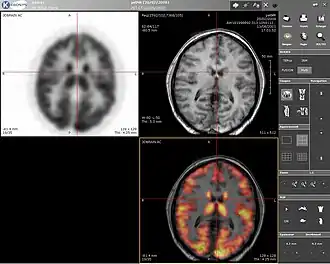

Positron emission tomography (PET) is a nuclear medicine imaging technique which produces a three-dimensional image or picture of functional processes in the body. The theory behind PET is simple enough. First a molecule is tagged with a positron emitting isotope. These positrons annihilate with nearby electrons, emitting two 511 keV photons, directed 180 degrees apart in opposite directions. These photons are then detected by the scanner, which can estimate the density of positron annihilations in a specific area. When enough interactions and annihilations have occurred, the density of the original molecule may be measured in that area. Typical isotopes include 11

F being the most clinically utilized. One of the major disadvantages of PET is that most of the probes must be made with a cyclotron. Most of these probes also have a half life measured in hours, forcing the cyclotron to be on site. These factors can make PET prohibitively expensive. PET imaging does have many advantages though. First and foremost is its sensitivity: a typical PET scanner can detect between 10−11 mol/L to 10−12 mol/L concentrations.